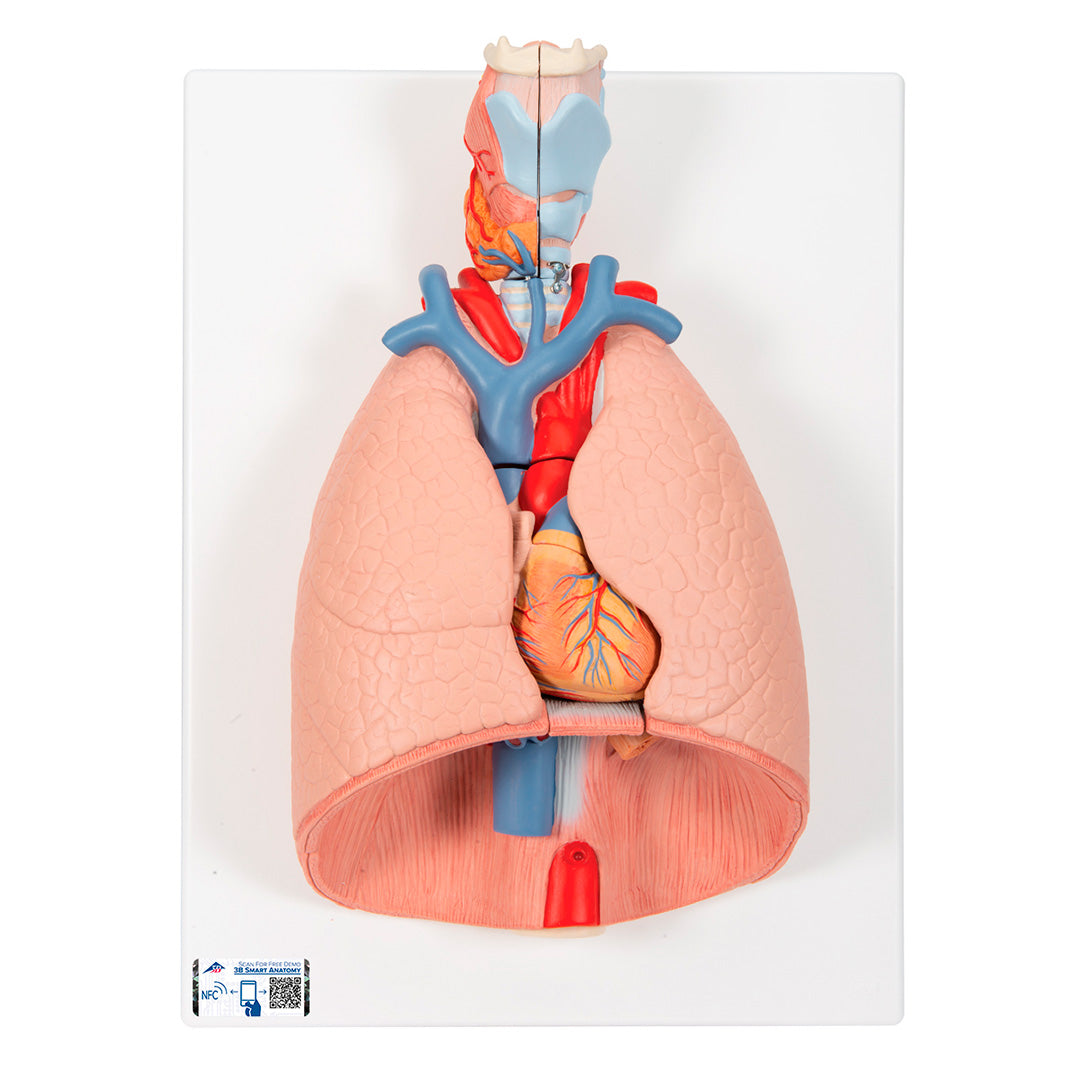

Modelo del pulmón, 7 piezas

Modelo del pulmón, 7 piezas

Descripción

Una sección aumentada y muy detallada a través de la mitad derecha del encéfalo, incluyendo una porción del cráneo.

Características

Peso: 1.845 kg

Dimensión: 41 x 31 x 12 cm